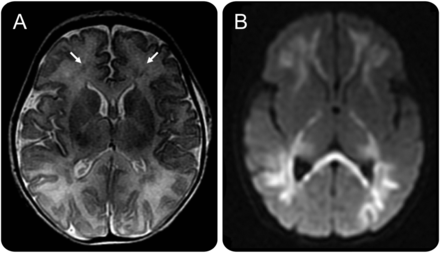

核磁共振的新生儿parechovirus脑炎

核磁共振t2加权旋转回声轴节(一个)显示点状的白质病变(箭头)暗示了瘀斑的出血。Diffusion-weighted成像部分(B)显示弥漫性高信号强度过度。这个独特的白质参与模式是值得注意的,这些异常延伸到皮层下白质,涉及整个纤维束,胼胝体、光学辐射,和后丘脑。

HPeV感染的诊断是由积极HPeV PCR在脑脊液和血液。广泛的白质异常是一个典型的MRI发现在新生儿HPeV脑炎,而单纯疱疹病毒脑炎展品扩散灰质和白质的变化。1